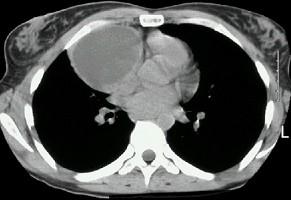

问题 女,18岁,自感胸闷,X光检查见纵隔占位,CT检查如图,最可能的诊断为 ( )

选项 A.纵隔畸胎瘤 B.上纵隔胸腺瘤 C.胸内甲状腺瘤 D.淋巴瘤 E.下纵隔胸腺瘤

答案 A